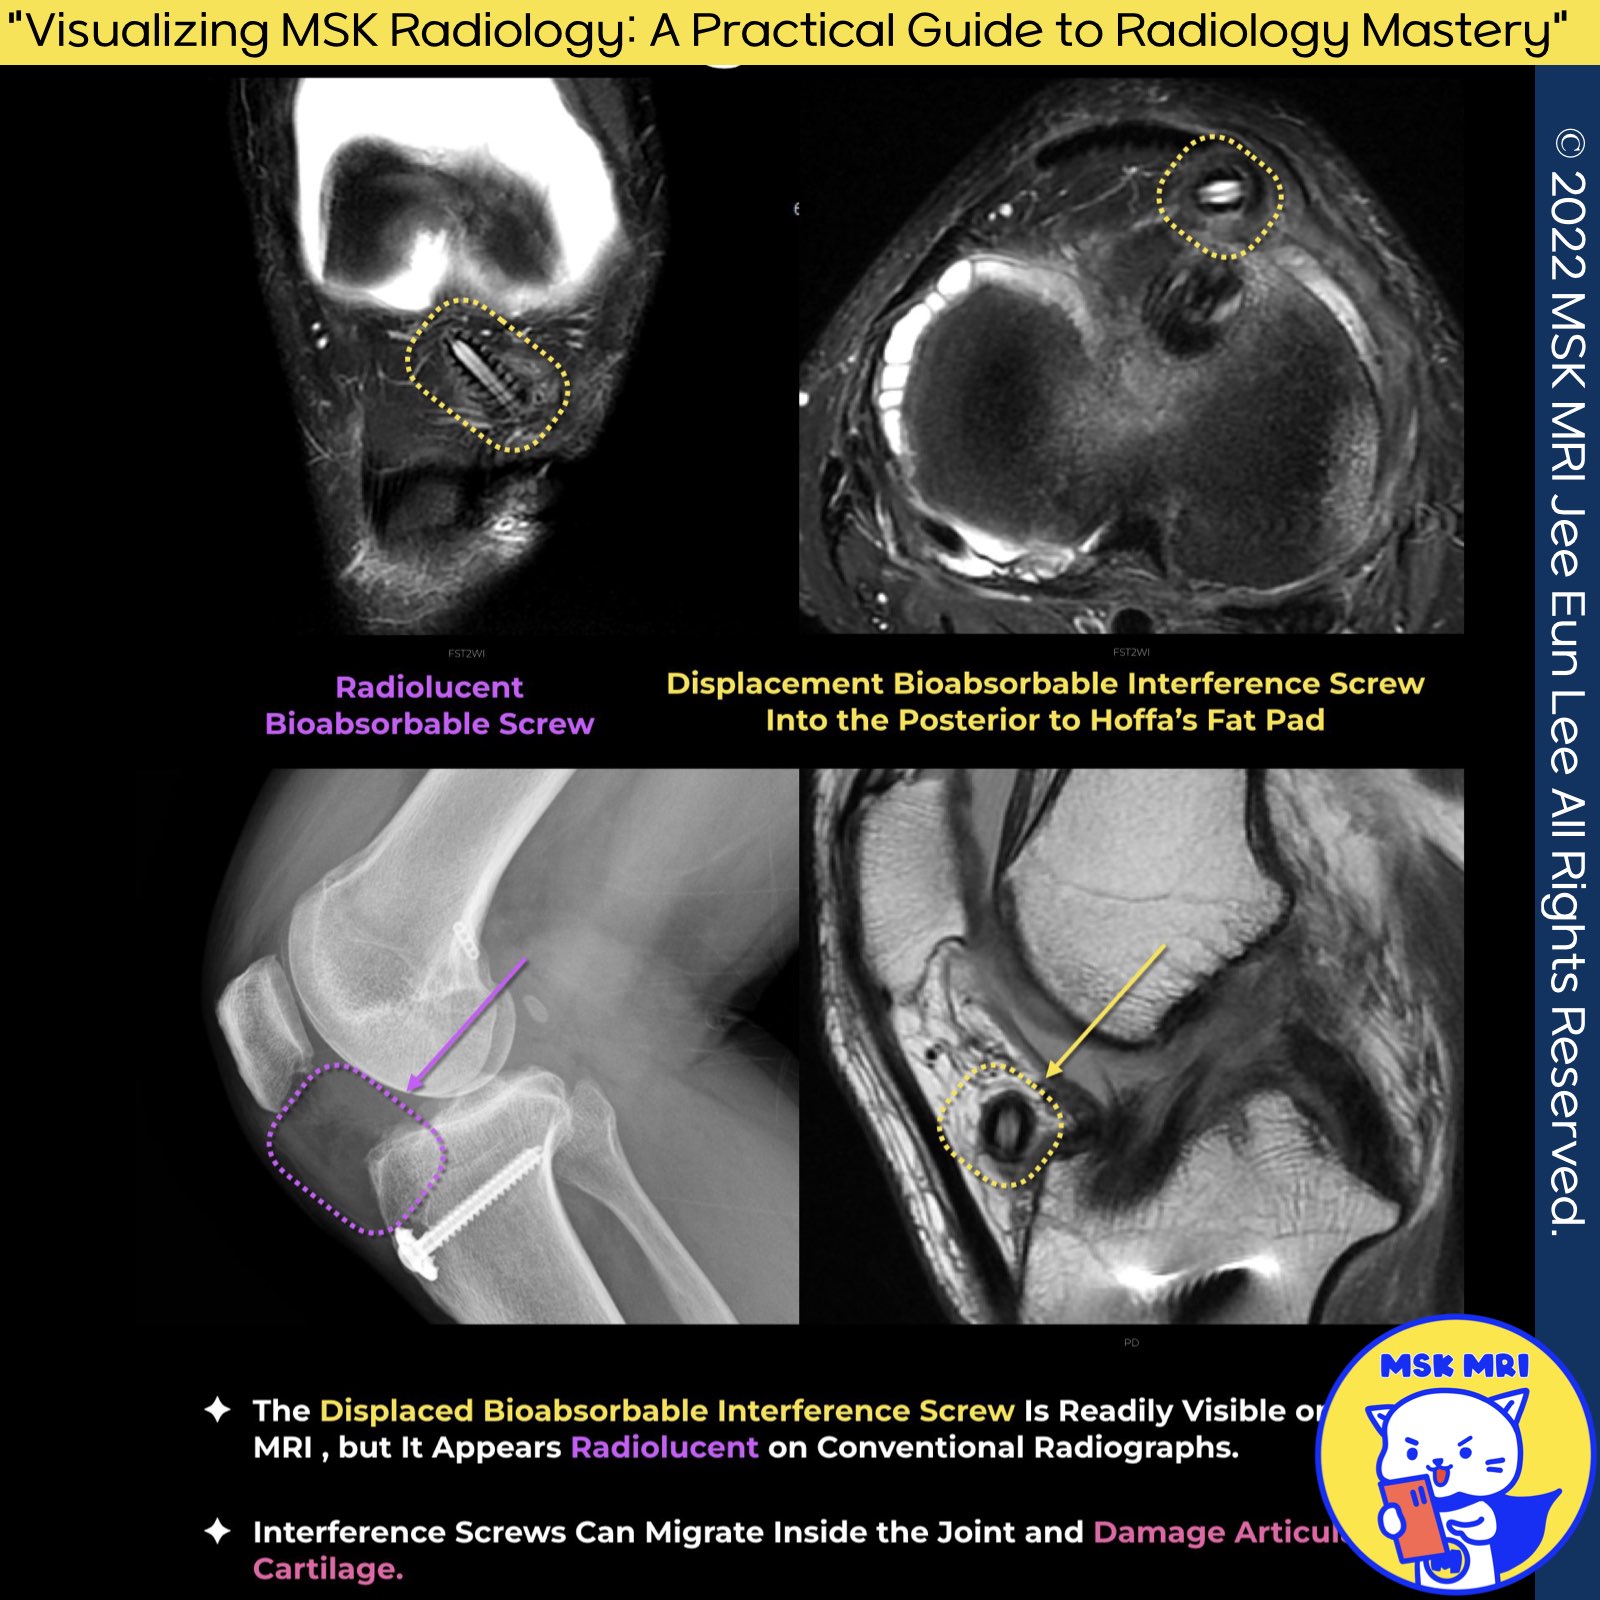

✅ Interference Screw Complications

- Fractures of interference screws and their migration within the site.

- Interference screws can migrate inside the joint, potentially damaging the articular cartilage.